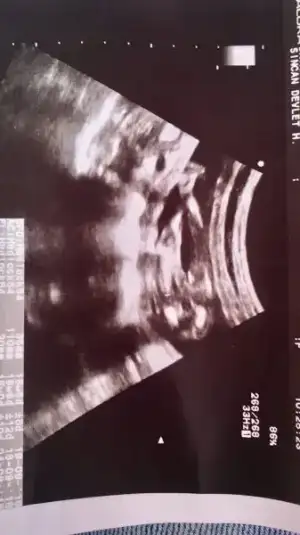

Anladim canim. Öyleymiş evet sağ olasin. Acil durum olursa ararsin dedi. Sağlıklı olsunlar da mevbur bekleyeceğiz.Ben de 12. haftamda kontole gitmiştim doktor 16. haftaya randevu verdi 3'lü tarama için canım. Herhangi bir sorun yoksa (kanama alanı falan gibi Allah korusun) genelde 1 ay sonraya veriyolar randevuyu![]()

Evet bu gebelikte öğrenmiş oldum. Ama daha doya doya göremedim hiç bebeğimi.Ben de ilkinde hep kanama sorunu nedeniyle rutin 2 haftada bir gitmiştim kontrole. Ama sorun olmayınca daha seyrek çağırıyolar![]()